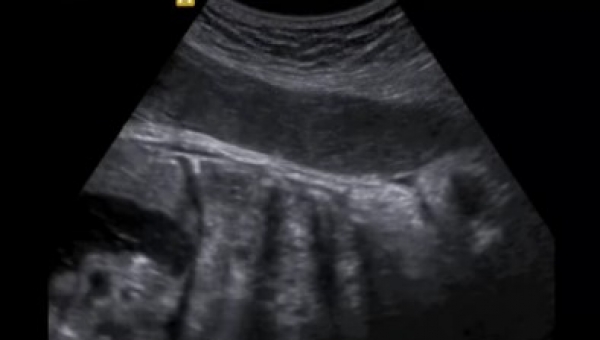

Es considerada una forma novedosa y potencialmente mortal de implantación anormal de un saco gestacional dentro del miometrio y el tejido fibroso de la cicatriz.

Hay quienes también le llaman “istmocele”, “embarazo ectópico en la cicatriz de la cesárea”. Sin embargo, algunos grupos prefieren hacer la diferencia con el embarazo ectópico “verdadero”: tubario, cornual, intersticial y cervical.